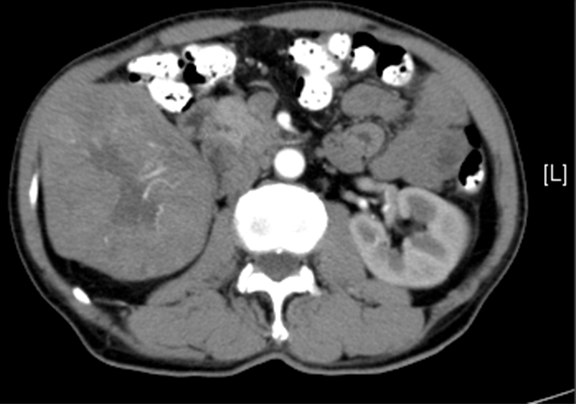

现病史:患者自述20天前,于当地医院健康查体,行血清肿瘤标志物检查示AFP31.71ng/ml,患者无乏力,无恶心、呕吐,无腹胀、腹泻,无寒战,无头痛头晕,无皮肤粘膜黄染,建议患者到上级医院就诊。遂就诊于黄岛区第二人民医院,行上腹部CT检查,诊断“肝占位性病变”。患者为求进一步诊治就诊于我院消化内科门诊,行上腹部增强CT,诊断:肝右叶占位性病变,考虑肝Ca并肝右静脉瘤栓,副脾肝内外胆管扩张。为行手术治疗收入我科。患者自发病以来精神状态一般,食欲较前无明显变化,睡眠良好,大、小便正常,体力情况良好,近1月体重下降约5kg。

上腹部动态增强CT:1. 肝右叶占位性病变,考虑肝Ca 并肝右静脉瘤栓可能性大,请结合临床2. 副脾3. 肝内外胆管扩张,必要时MRCP检查4. 胰腺颈部小囊状低密度影,建议MRI 检查

术前CT检查:

动脉期

静脉期

平衡期